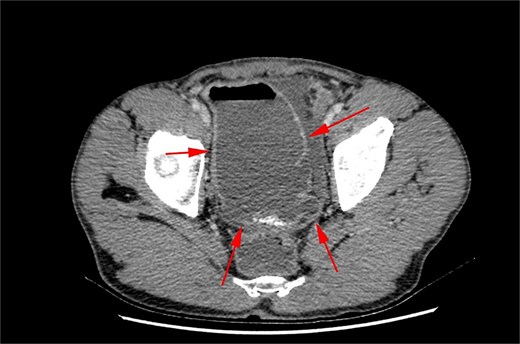

An intraoperative diagnosis of acute ruptured appendicitis with and giant MD was made. An appendectomy was performed, followed by a segmental ileal resection incorporating the diverticulum (Fig. 4). A primary, end-to-end, hand-sewn, single-layer ileo-ileal anastomosis was constructed using 2–0 silk.

The postoperative course was unremarkable, and the patient was discharged on day three. Gross pathological examination revealed a T-shaped segment of the small bowel, including a segment continuous with a 23 × 13 cm dilated portion. Histological appraisal revealed an evagination of the wall involving all layers, accompanied by significant oedema and congestion of the submucosa. No heterotopic mucosa was identified. Acute inflammation and fibrin deposition were observed in the serosa. These findings were consistent with Giant MD with diverticulitis. The vermiform appendix specimen exhibited acute inflammatory changes with neutrophilic infiltration across all layers, indicative of acute appendicitis.